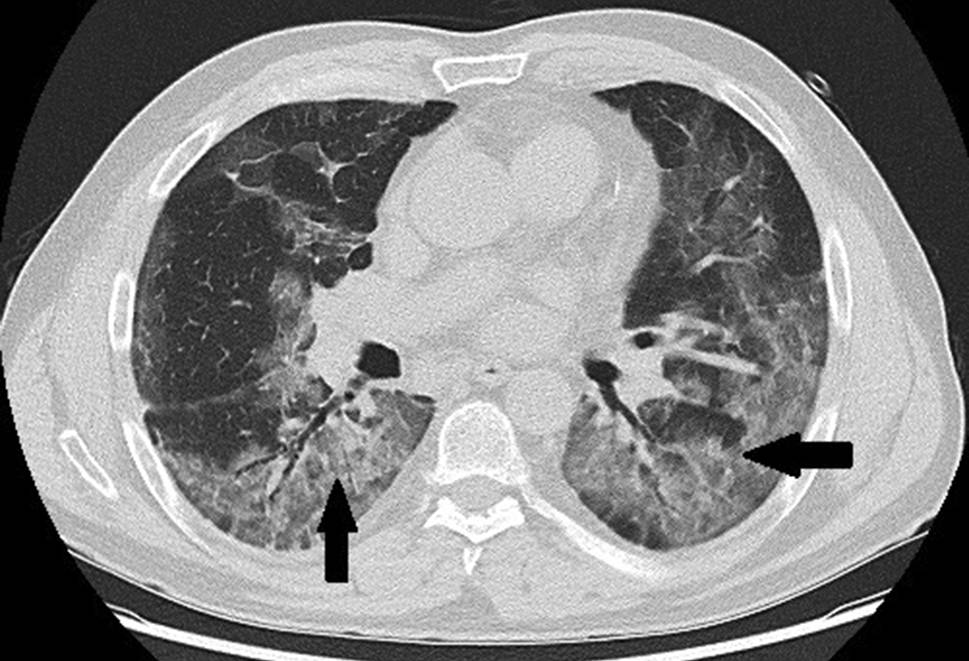

Das Thorax-CT am Aufnahmetag zeigte bilaterale milchglasartige Verschattungen. Antibiose mit Piperacillin/Tazobactam wurde eingeleitet. Unter High-flow-Sauerstofftherapie stabilisierte sich die O2-Sättigung bei 92 %. Am Tag 9 entstand eine respiratorische Dekompensation. Nach Stoßtherapie mit 1 g Methylprednisolon über 4 Tage und anschießender Gabe von Prednisolon 50 mg täglich sowie Masken-CPAP-Atmung stabilisierte sich die respiratorische Situation. Das Kontroll-Thorax-CT zeigte Zunahme der Infiltrate, ein Pneumomediastinum und einen minimalen linksseitigen Pneumothorax (Abb. 3). Eine linksseitige Thoraxdrainage wurde gelegt. Am Tag 14 entstand rapide eine respiratorische Globalinsuffizienz, sodass Intubation und in weiterer Folge die Anlage eines Tracheostomas erforderlich wurden.

Abb. 3

Pneumomediastinum (Pfeil), schmaler Pneumothorax (2 Pfeile)

Trotz expandierter Lunge und Regredienz des Mediastinalemphysems persistierten Decarboxylierungs- (pCO2 55–95 mm Hg) und Oxygenierungsprobleme (OI 90–120). Bei liegender Thoraxdrainage entwickelte sich 5 Tage später ein neuerlicher, apikal gekammerter Pneumothorax (Abb. 4), der gezielt mit einer weiteren Drainage versorgt wurde. Nach 16 Tagen Beatmung über den Tubus („dual positive airway pressure“, Spitzendrücke 30 mbar, durchschnittlicher „driving pressure“ 18 mbar) ohne eindeutige Besserungstendenz der respiratorischen Situation und bei weiterer Verschlechterung der Hämodynamik trotz kontinuierlich steigender Katecholamindosen verstarb der Patient am Tag 31 der intensivmedizinischen Behandlung an einer abdominellen Blutungskomplikation.

Abb. 4

Pneumothorax (Pfeil) trotz liegender Thoraxdrainage (Stern). Das diskrete Weichteilemphysem in den Mm. pectorales beidseits ist in diesem Fall Folge der Tracheostomie